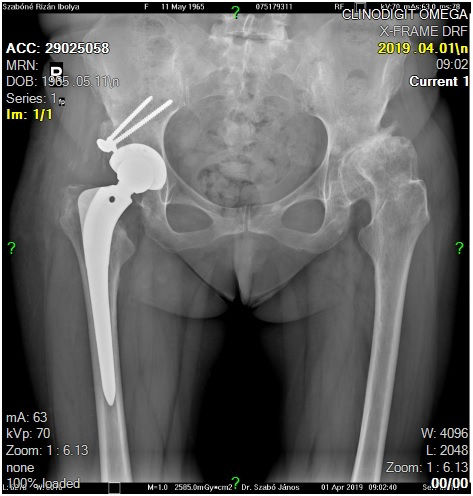

29 éves pályám során közel ezer térdprotézist és több mint kétezer csípőprotézist ültettem be. Az utóbbi években egyre több, nagy műszer igényű, összetett protézis revíziós műtétet végzek.